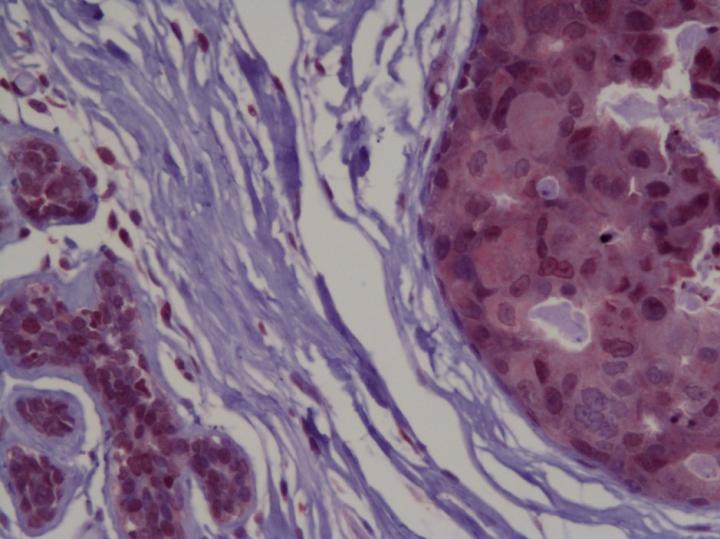

The researchers used a special staining process on breast cancer tissue removed during biopsy to observe the levels and location of PRH proteins in breast cancer cells. They found that in a small study there were changes in PRH proteins in tumour cells compared to normal cells that were consistent with the decreased activity of the PRH gene in the public database.